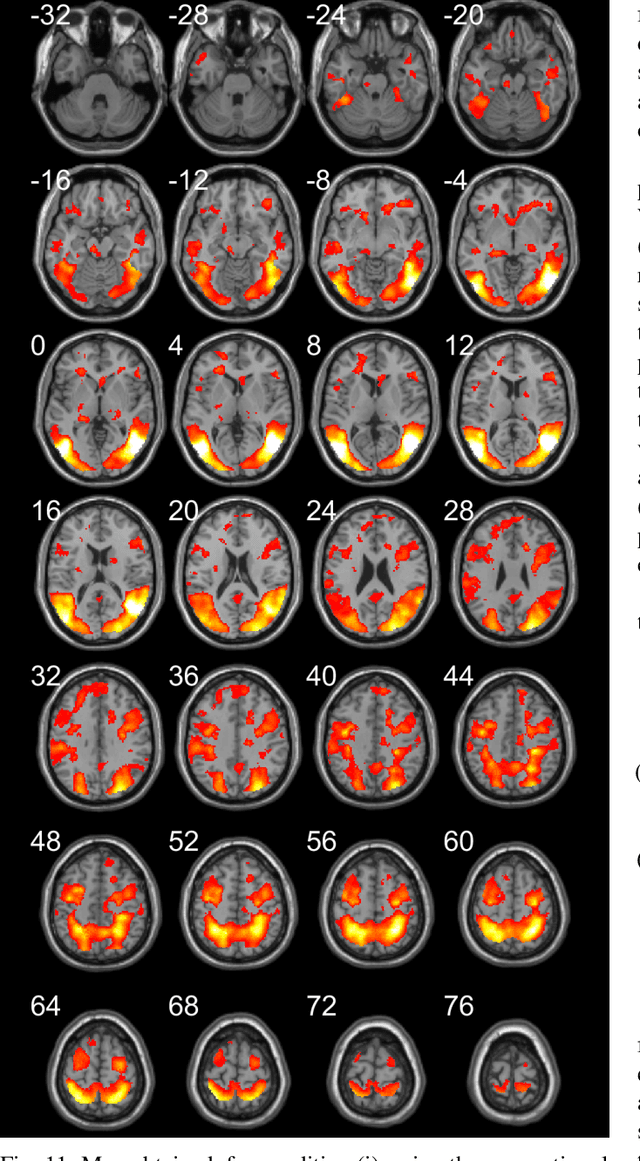

Abstract:Functional magnetic resonance imaging (fMRI) is one of the most popular methods for studying the human brain. Task-related fMRI data processing aims to determine which brain areas are activated when a specific task is performed and is usually based on the Blood Oxygen Level Dependent (BOLD) signal. The background BOLD signal also reflects systematic fluctuations in regional brain activity which are attributed to the existence of resting-state brain networks. We propose a new fMRI data generating model which takes into consideration the existence of common task-related and resting-state components. We first estimate the common task-related temporal component, via two successive stages of generalized canonical correlation analysis and, then, we estimate the common task-related spatial component, leading to a task-related activation map. The experimental tests of our method with synthetic data reveal that we are able to obtain very accurate temporal and spatial estimates even at very low Signal to Noise Ratio (SNR), which is usually the case in fMRI data processing. The tests with real-world fMRI data show significant advantages over standard procedures based on General Linear Models (GLMs).